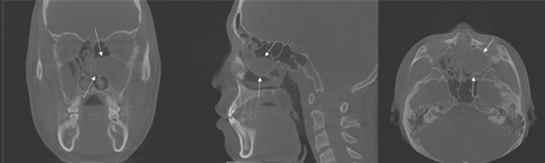

14세 남아의 왼쪽 상악동에 생긴 점액낭종 분석 영상이미지(사진제공=경희대치과병원) ⓒ 뉴스1